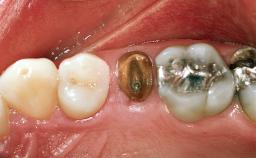

Replacement of a Maxillary Right Central Incisor Using an Early Loading Protocol

A healthy 26-year-old woman was referred for evaluation and treatment of her failing maxillary right central incisor (tooth 11). She reportedly traumatized the tooth at about age 9 and subsequently had repeated conventional and surgical endodontic procedures and fixed restorations. Despite these procedures, she had recurrent fistulas in the apical mucosa and a mid-facial pocket of 7 mm with suppuration. All other sites on the tooth probed 3 mm without inflammation. She presented with a medium biotype with triangularlyshaped teeth and a moderately high smile line, showing all of her papillas and a few millimeters of marginal gingiva in a full smile.Ceramic veneers were present on teeth 12, 21, and 22, and they were known to be somewhat bulky, eventually requiring replacement. She had a strong desire to avoid additional tooth preparation and would not consider a fixed dental prosthesis to replace tooth 11.

Loading Protocol Conventional or early

Provisional Implant-Supported Prosthesis Prosthodontic margin > 3 mm apical to mucosal margin Prosthodontic margin > 3 mm apical to mucosal margin